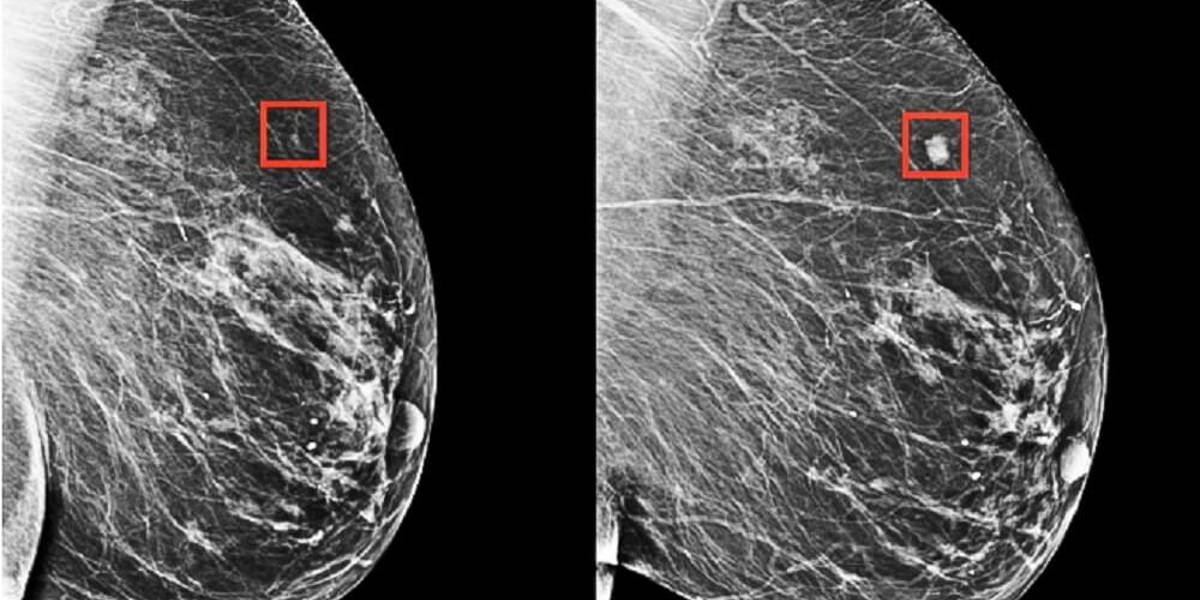

The model detected patterns too subtle for the human eye to detect

Rather than manually identifying the patterns in a mammogram that drive future cancer, the MIT/MGH team trained a deep-learning model to deduce the patterns directly from the data. Using information from more than 90,000 mammograms, the model detected patterns too subtle for the human eye to detect.

The team's model was shown to be able to identify a woman at high risk of breast cancer four years (left) before it developed (right) (image courtesy of the researchers).